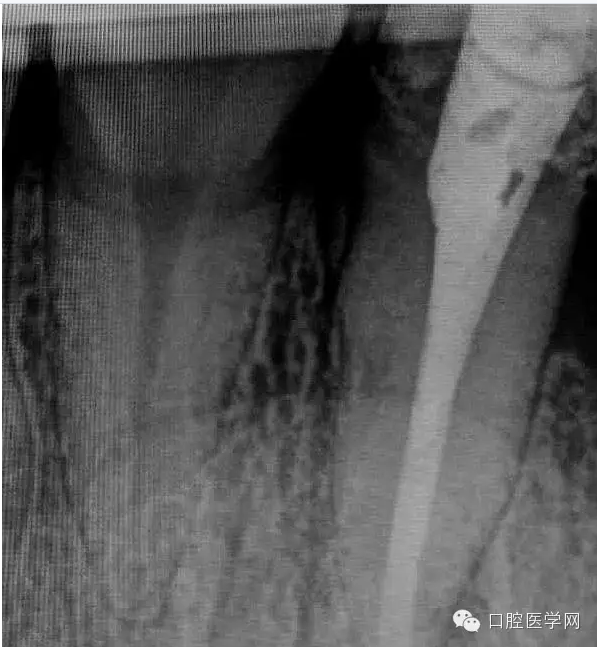

患牙有嚴(yán)重叩診不適。根尖片明確的顯示了牙根根尖喇叭口及根尖均有低密度影像。2年前有外傷史,右上側(cè)切牙缺失。

2年前,患牙曾經(jīng)就多次進(jìn)行過(guò)根管治療。就一直隱隱疼痛不適,不見(jiàn)好轉(zhuǎn)!經(jīng)轉(zhuǎn)診醫(yī)生介紹一封藥就腫痛不適!